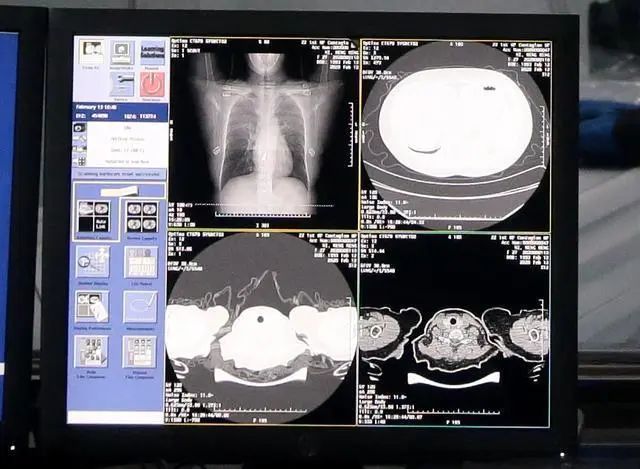

這些身懷絕技的機(jī)器人離不開它的核心技術(shù),就是人工智能AI。AI在此次疫情的醫(yī)療診斷和結(jié)果分析上也是大顯身手。武漢火神山醫(yī)院上線的達(dá)摩院AI,就大大提高救治效率,降低病死率,實(shí)現(xiàn)精準(zhǔn)診斷。

阿里巴巴集團(tuán)科技線公關(guān)林俊特:20秒就能給出96%準(zhǔn)確度的CT影像分析結(jié)果,可精準(zhǔn)識(shí)別病灶位置并算出病灶占比的變化數(shù)值,捕捉患者治療全程病情變化的蛛絲馬跡。AI診斷覆蓋新冠患者入院到出院全過(guò)程,幫助醫(yī)生及時(shí)調(diào)整診療方案,降低重癥轉(zhuǎn)化率。

達(dá)摩院AI的CT影像分析結(jié)果